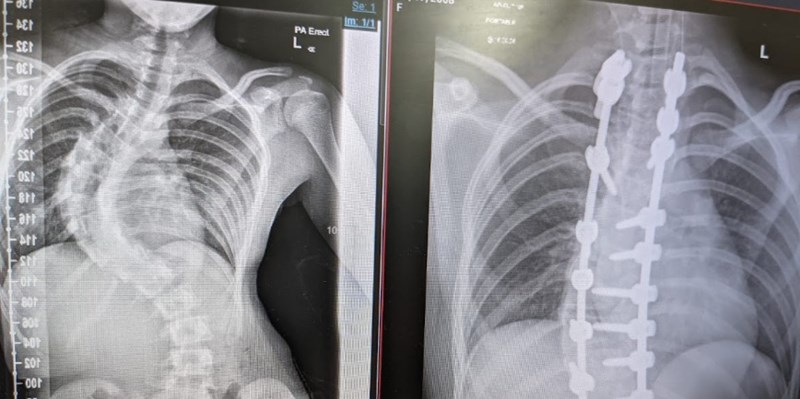

We were lucky enough to receive surgery for Olivia's scoliosis at Birmingham Children's Hospital this year, it was a life changing operation (in a good way) for both her and for us.